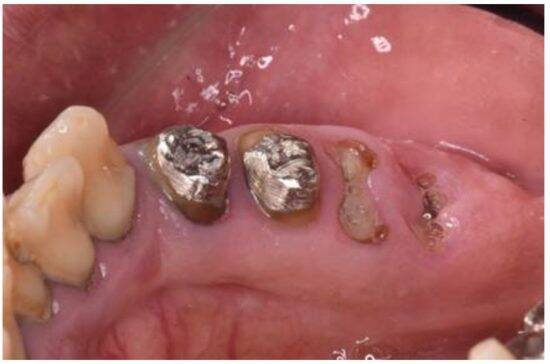

保険診療のクオリティは、やはり自費診療には敵わず、銀歯の下でむし歯が再発する「二次カリエス」のリスクや、見た目年齢への影響もあります。

海外では、保険診療という概念がないため、日本の銀歯は不思議がられることも多いです。時間コスト・再治療コスト・見た目の損失が大きいという難点があるのです。